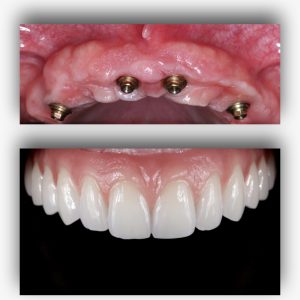

A implantodontia é um procedimento odontológico que envolve a colocação de implantes dentários de titânio no osso maxilar ou mandibular para substituir dentes perdidos. Os implantes proporcionam uma base sólida para a fixação de coroas, pontes ou próteses, restaurando a função mastigatória, estética e saúde bucal do paciente.